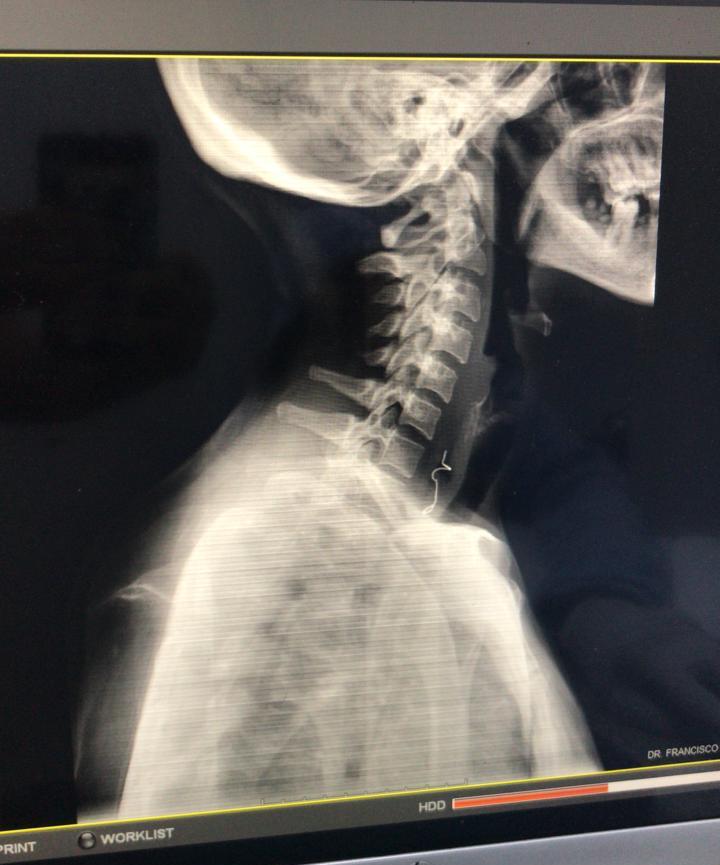

Tras tener alojado en el esófago su prótesis dental, una mujer de 43 años fue intervenida quirúrgicamente de forma exitosa por cirujanos del hospital docente universitario doctor Francisco E. Moscoso Puello.

Durante la cirugía se desbridó un 10% de tejido desvitalizado del esófago secundario, debido a que la prótesis dental utilizó músculos del cuello como colgajos.